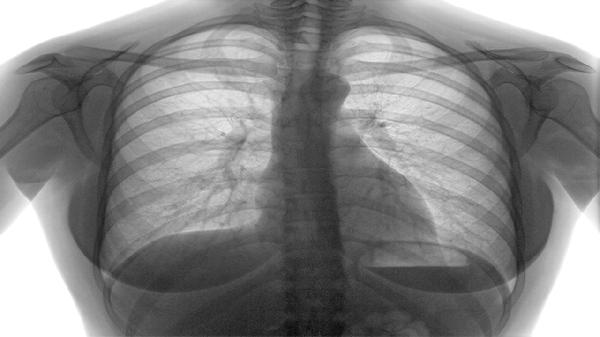

肺结节MIA,或称为微浸润腺癌,通常是可以治疗的。MIA在影像学上常表现为磨玻璃影,这种影像可能意味着肺部存在轻微的密度增高,看起来像云雾一般。它可能是良性病变的标志,也可能是恶性的信号。关键在于准确诊断和及时治疗。